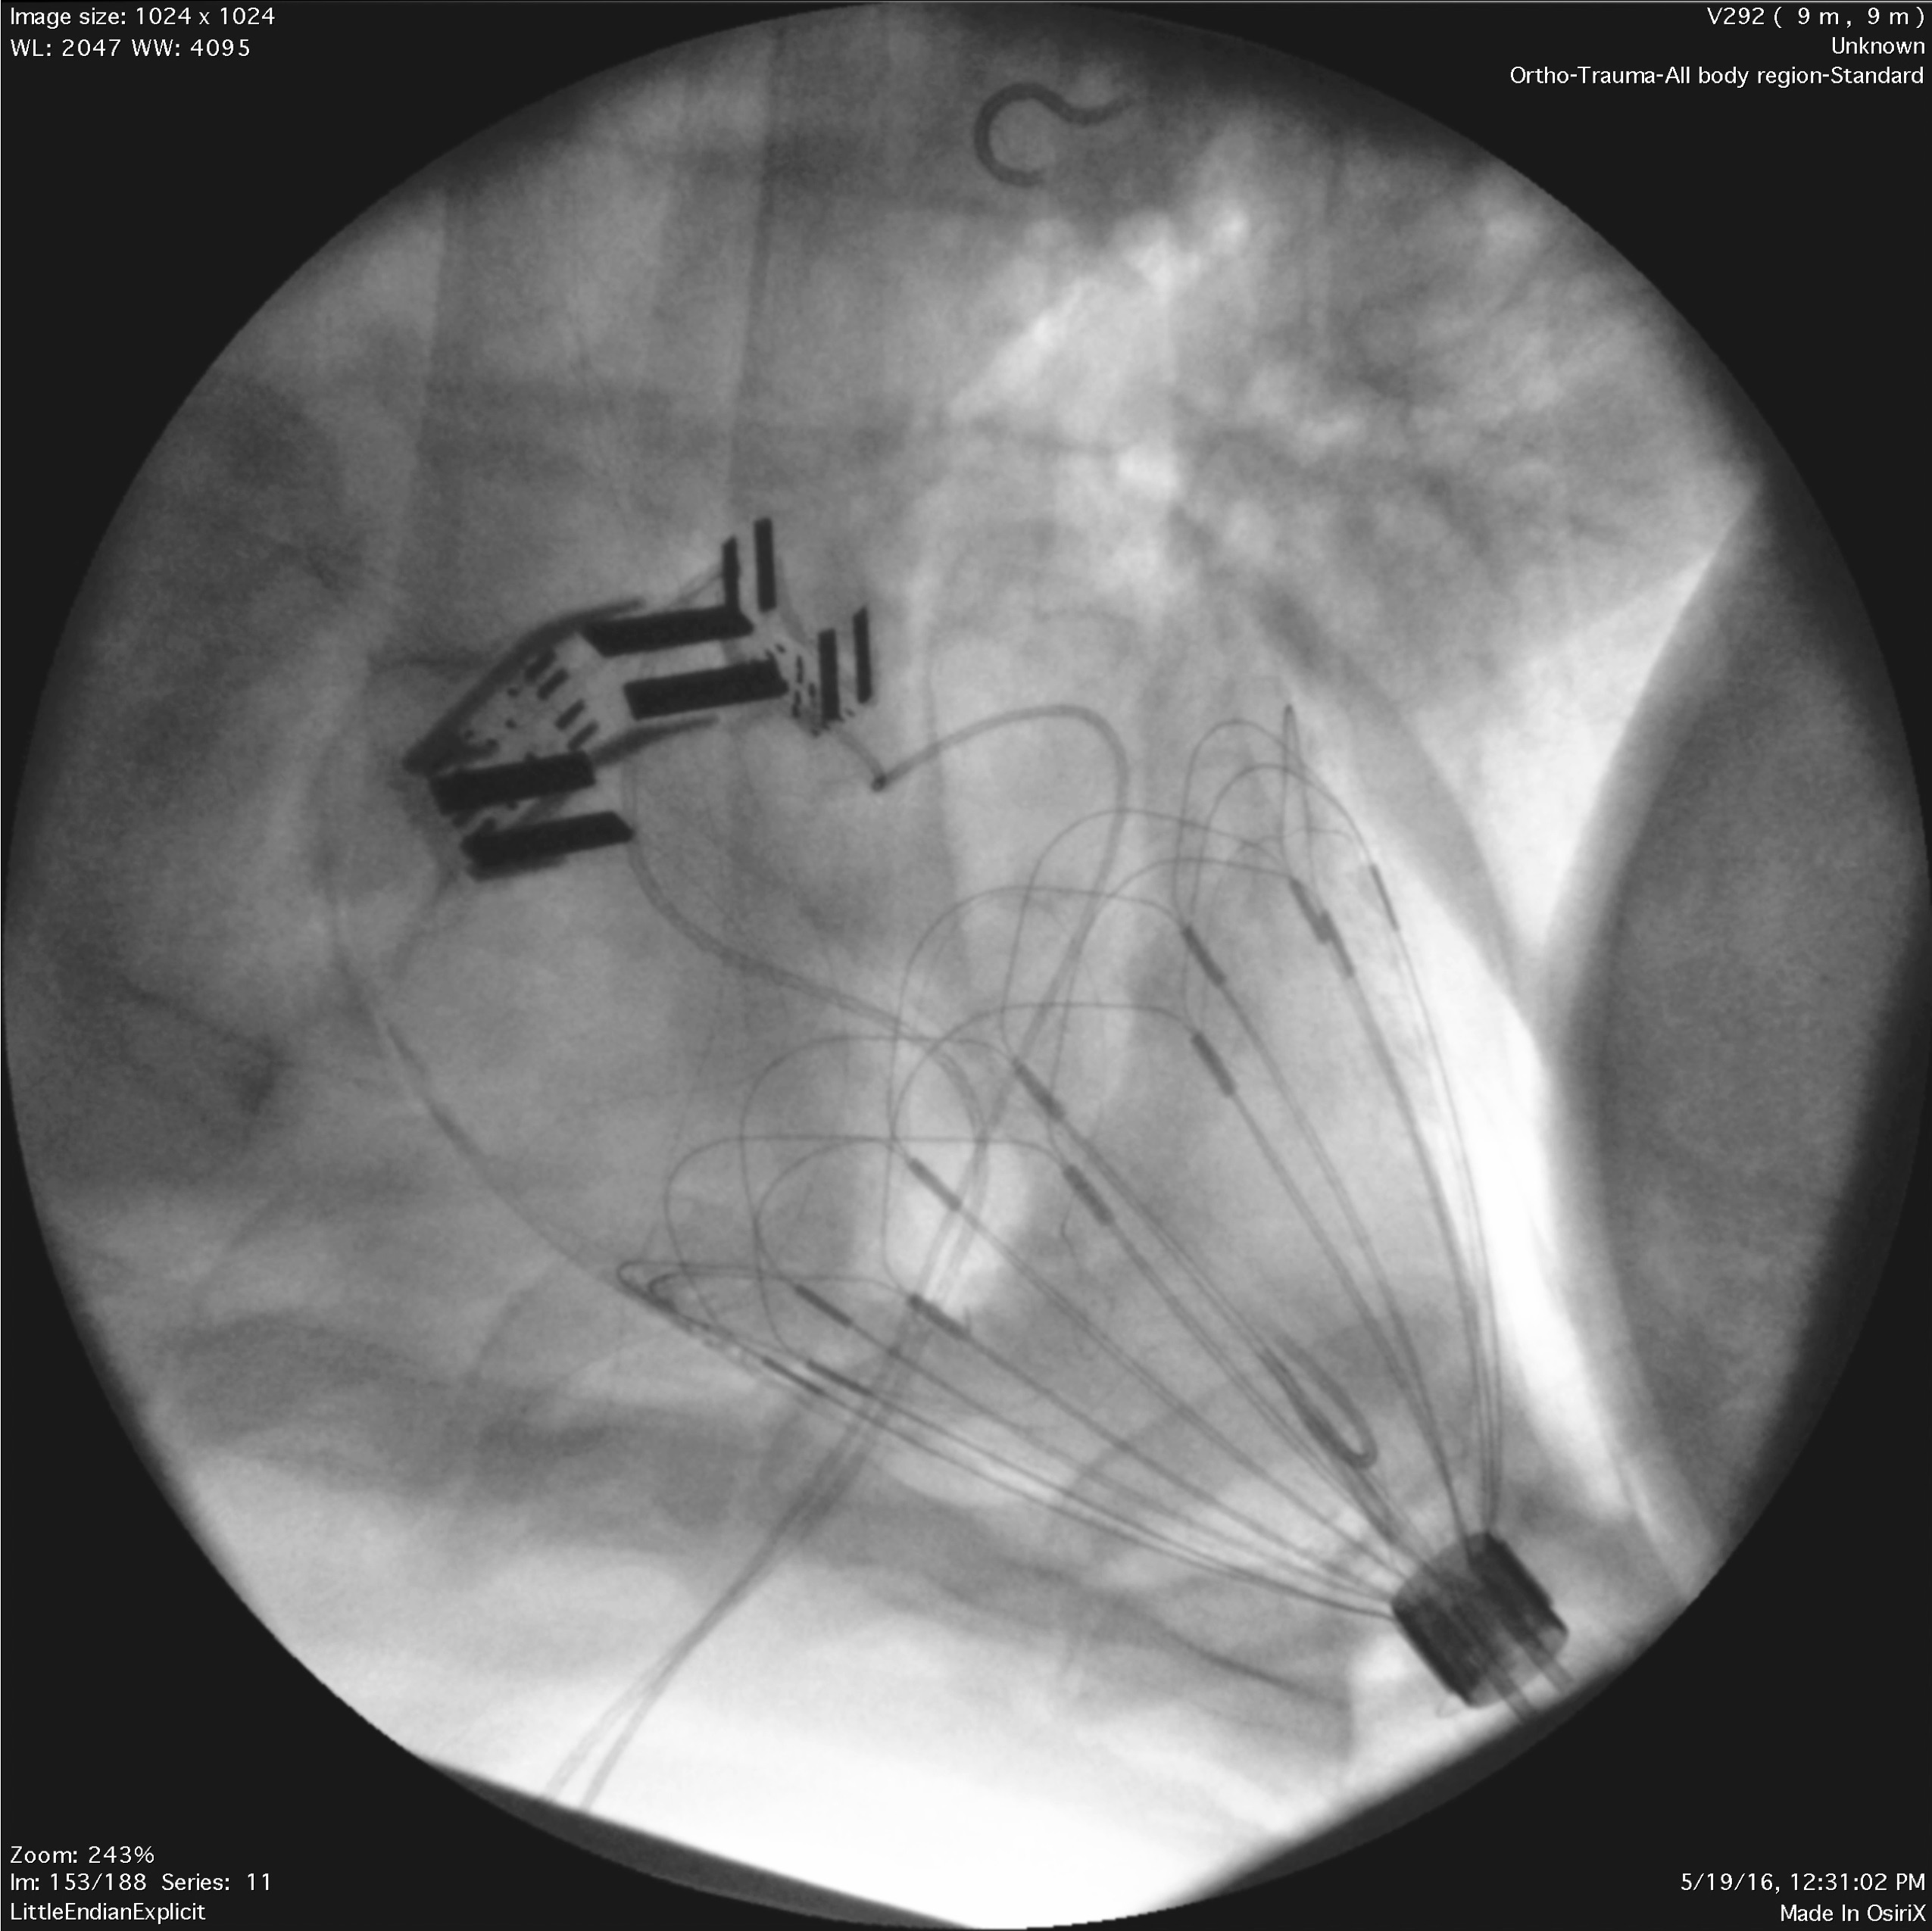

A black and white medical scan shows an expanding mechanical device inside a patient’s body.

Criscione’s compression device expanding to fit around a patient’s heart. | Image: Photo courtesy of Dr. John Criscione.

Criscione and Perez are working to improve these odds by taking an entirely different approach using an internal compression device placed around the patient's heart. By assisting the heart from the outside, the device would work with the patient’s natural system, rather than bypassing it. Because it does not come in direct contact with the bloodstream, the device has the potential to decrease clots, leaks and infections that often accompany external machines.